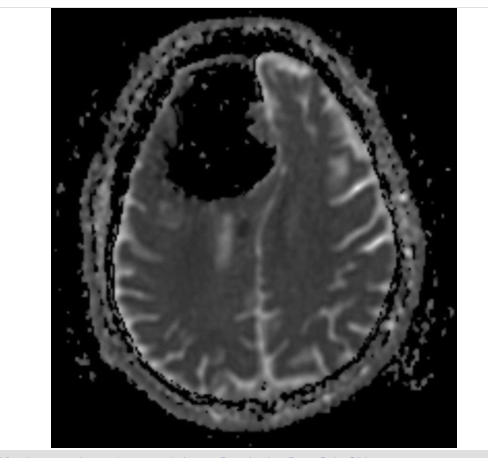

Baş ağrısının yanı sıra sol tarafında bir ağrı ve yürümede sıkıntı yaşayan hastanın röntgeni kısa sürede çekildi. Fakat doktorlar röntgeni inceledikten sonra tıp tarihinde eşi benzerine çok zor rastlanan bir sonuçla karşılaştı. Doktorlar, 84 yaşındaki hastanın beyninin sol tarafının olmadığını fark etti.

Baş ağrısı diye hasteneye gitti beyinsiz çıktı! - Resim: 4

Hayatı boyunca sigara içmeyen ve nadiren alkol alan adamda görüş bozukluğu, konuşma ya da görsel rahatsızlıkları olmadığını açıklayan doktorlar, “O günlük fiziksel aktivitelerini aksatmadan yapan, sağlıklı bir haldeydi. Fakat yapılan testler sonucunda biz de çok şaşırdık” ifadesini kullandı.